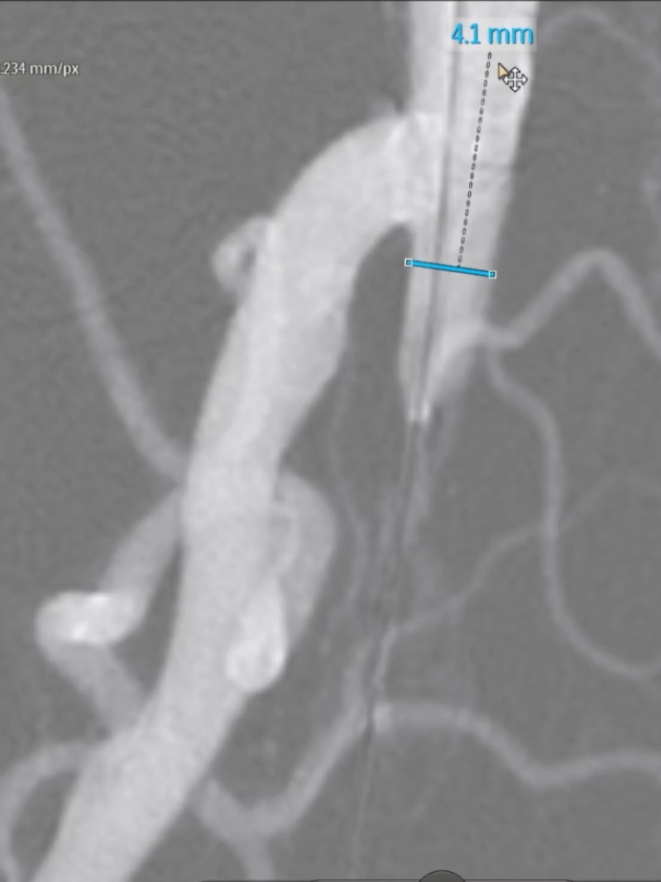

预扩张:使用球囊扩张病变段,造影提示长段限流性夹层,需支架覆盖

治疗模式:因股腘动脉直径<4.5mm,选择DCB(药物涂层球囊)+BMS(裸金属支架)联合方案;

支架选择:在DCB扩张导管进行管腔准备后,植入2枚5mm INNOVA支架,其优势在于尾端定位精准,尤其适合累及开口或分叉的病变。